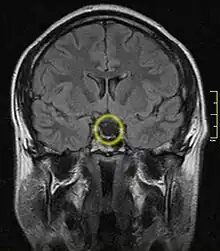

| Empty sella turcica on MRI as seen in severe cases of Sheehan's syndrome | |

MRI is useful in diagnosing Sheehan's syndrome since it examines the structure of the pituitary and may identify any anatomical damage.[4] MRI findings will vary based on how early or late in the disease process the test is being conducted. If an MRI is conducted early enough in the disease process the pituitary may appear larger than normal, and show changes that are consistent with damage from lack of blood supply.[15] Later in the disease process of this syndrome the damage imposed on the pituitary gland will cause it to shrink, and leave a partially empty or totally empty sella turcica on MRI.[7]